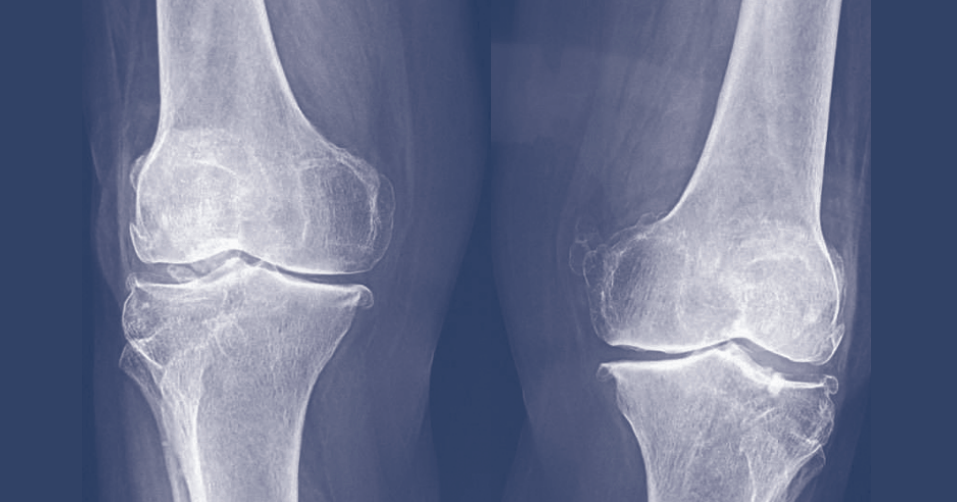

Il progressivo invecchiamento della popolazione richiede una attenta gestione del malato. Non bisogna dimenticare che il malato complesso presenta gravi comorbilità come le patologie osteoarticolari in particolare l'osteoporosi e l'artrosi. L'osteoporosi è una patologia geriatrica di rilevante impatto sanitario e sociale, che deve essere tempestivamente diagnosticata e trattata con l'obiettivo di ridurre in maniera significativa il numero di fratture da fragilità. L'utilizzo di vitamina D e di bifosfanati è limitato però dalle note che spesso mettono in difficoltà il medico di famiglia. Scopo dell'incontro è passare in rassegna le possibili soluzioni per questi problemi, fornendo al medico delle indicazioni precise in base alla Evidence Based Medicine.